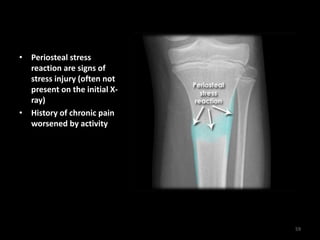

Tibial stress fracture

58

• Periosteal stress

reaction are signs of

stress injury (often not

present on the initial X-

ray)

• History of chronic pain

worsened by activity